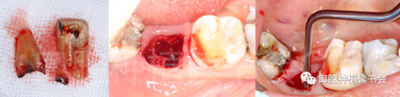

5.3.1 使用球鉆及帶有定深器的先鋒鉆在根分叉上方定點(diǎn)、定深,確定方向(圖14)。

圖14 選擇在殘根根分叉上方定點(diǎn),先鋒鉆預(yù)備方向。

5.3.2 逐級預(yù)備種植窩洞后,側(cè)切鉆分根,微創(chuàng)拔除殘根,探查頰、舌側(cè)骨板完整,仔細(xì)搔刮拔牙窩,生理鹽水沖洗(圖15)。

圖15 微創(chuàng)拔牙后確認(rèn)種植窩洞位于牙槽間隔內(nèi)。